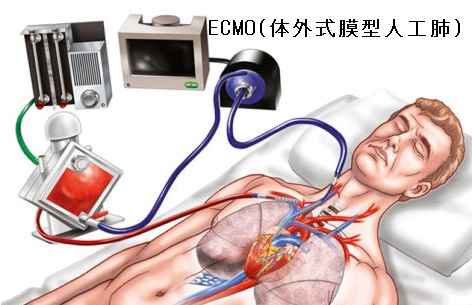

巨大甲状腺腫や高度肥満による気道狭窄で甲状腺切除手術の気道確保困難(挿管困難)が予測される場合、VV-ECMO(体外式膜型人工肺)開始後、気管支鏡を用い挿管。内臓逆位では心血管・消化器系の奇形を合併しなくても左右の反回神経の走行が逆になるため注意。巨大甲状腺腫、甲状腺癌の転移・浸潤が胸骨に及ぶ場合、胸骨切開(全切開、部分切開)/胸骨切除が必要。甲状腺手術の皮膚縫合は美容上の問題から形成外科が行う事も。甲状腺の病気があれば経皮経食道胃管挿入術(PTEG/ピーテグ)は禁忌。海外では甲状腺摘出術後の頸部創傷治癒促進と瘢痕形成抑制にPRP療法。

巨大甲状腺腫、甲状腺腫瘍や高度肥満による気管の圧迫・気道狭窄(最狭窄部1cm以下)のため、甲状腺切除手術における気道確保困難(挿管困難)が予測される場合、

- V-ECMO(体外式膜型人工肺)補助下に気道確保を行う[Cureus. 2023 Feb 21;15(2):e35278.]

ECMO(extra-corporeal membrane oxygenation:体外式膜型人工肺)は、人工肺とポンプによる体外循環を行う装置で、1分間に数リットルの血液が循環します。

- VV-ECMO;肺炎などで肺の機能を補助する場合、静脈(Venous)から静脈(V)に血液を送る。重症化した新型コロナウイルス肺炎で使用されます。

- VA-ECMO;心臓の機能を補助する場合、静脈(V)から動脈(Artery)に血液を送る

回路内に血栓ができていないか小まめにチェックし、背中側の肺が悪くならないよう数時間おきに患者をうつ伏せ(腹臥位)にします(6-8人掛かりで慎重に体位変換)。人手がいくらあっても足りません。

VV-ECMOは、

- 詰まりにくい大口径カニューレがよい

- 回路内に血栓症ができるのを防ぐため、抗凝固療法が必要なので、圧迫止血し難い鼻腔吸引・胸腔ドレナージを避ける

- 導入後はVILI(呼吸器関連肺傷害)を予防し、肺を休めるため、弱い人工呼吸器設定(Lung rest)にする

- 酸素交換した血液を再度脱血しないよう(リサーキュレーション率を小さくするよう)、脱血、総血カニューレの置を離す

- 1週間以上、人工呼吸器管理し、VILI(呼吸器関連肺傷害)を受けた肺にVV-ECMOを導入しても予後不良が多い

気道狭窄を伴い手術予定の巨大甲状腺腫患者が、間に合わず心肺停止した際、挿管困難が予想されたため、体外式膜型人工肺(extracorporeal membrane oxygenation:ECMO)下に緊急気管切開術をおこなった。それでも不十分なので、甲状腺腫減量術(いきなりここまでやる救命病棟すごいわ。救命病棟24時がノンフィクションに近いのが納得できます)を追加して救命できた報告があります。ECMOがあればこそ可能な処置とも言えます。(Jpn J Respir Care 2019;36:173-7.)

甲状腺癌の浸潤による高度気管狭窄で気管切除・形成手術を行う場合、気管内挿管も手術自体も困難です。ECMO補助下に術野から離れた場所を気管切開し、気道確保した報告例があります(耳鼻咽喉科臨床 2016;109(3):195-201)(麻酔 2013;62(1):78-82.)

再発を繰り返す甲状腺がんの気管浸潤による高度気管狭窄で、気管内ステントを留置する時にもVV-ECMOが有用です(麻酔 2016;65(2):142-145)。